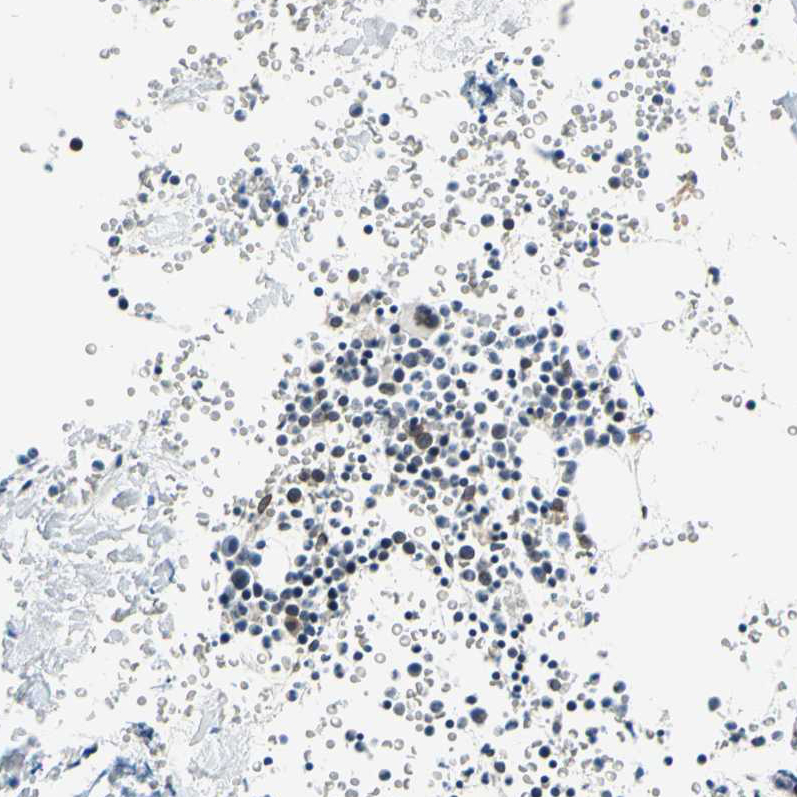

Immunohistochemistry analysis in human skin and bone marrow tissues using HPA008461 antibody. Corresponding SUN1 RNA-seq data are presented for the same tissues.